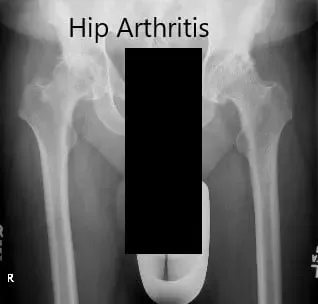

Los estudios de imagen revelaron osteoartritis bilateral severa de las caderas con quistes subcondrales, esclerosis y osteófitos. Teniendo en cuenta el dolor de cadera que limita el estilo de vida, le recomendaron una prótesis total bilateral. Ella aceptó seguir adelante con el procedimiento.

Radiografía preoperatoria que muestra la vista AP de la pelvis con ambas caderas.